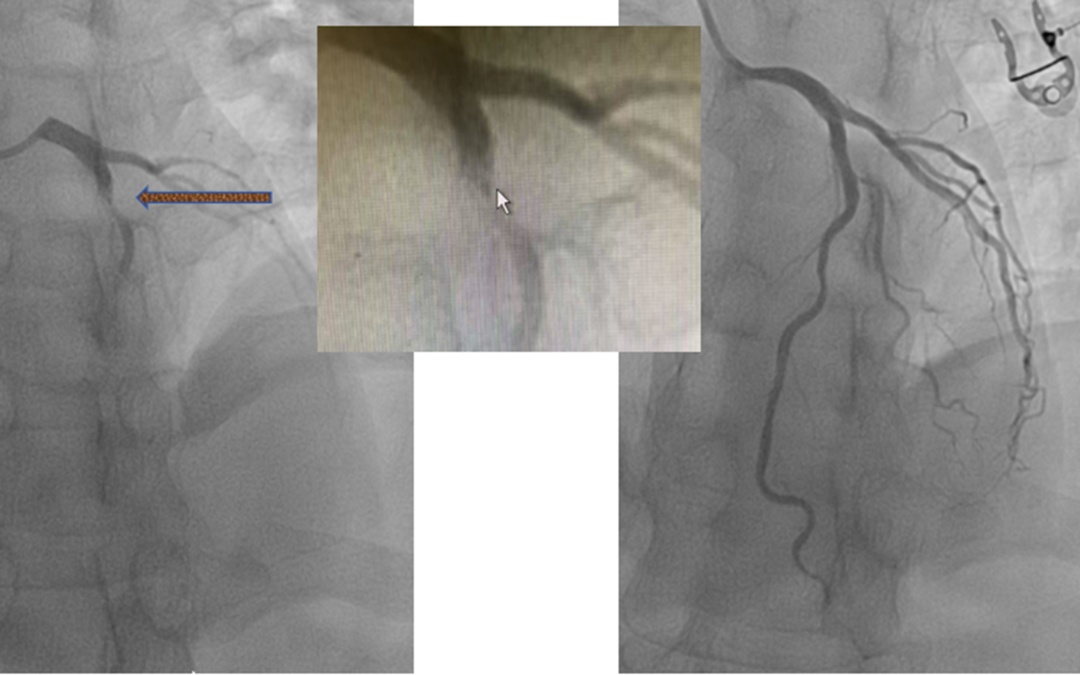

心血管内科介入团队接到指令后,迅速集结,以最快的速度投入手术。团队成员凭借精湛的介入技术,精准定位闭塞血管,在最短时间内成功开通患者闭塞的冠状动脉,恢复了心肌供血。当手术顺利完成,患者胸痛症状明显缓解时,在场医护人员悬着的心才终于落了地。此时,距离患者就诊仅数十分钟,这数十分钟里,医护人员与死神展开了一场激烈的赛跑,最终赢得了胜利。